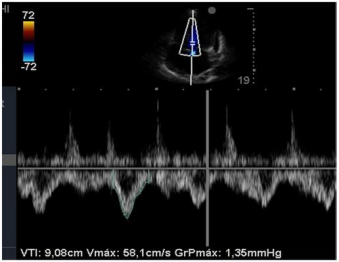

Insonação cardíaca Janela apical 5 câmaras com VTI de 9,08 cm

O nefrologista foi chamado a opinar na melhor conduta para o paciente. Para tanto, realizou uma ultrassonografia beira leito pulmonar e mensurou a velocidade integral tempo (VTI) do trato de saída do ventrículo esquerdo. Chegou, assim, à conclusão que poderia ser feita uma expansão no paciente. Com base nas imagens apresentadas, é correto afirmar que conduta recomendada pelo nefrologista está